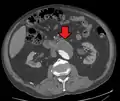

Abdominal aortic endoprosthesis, CT scan, original aneurysm marked in blue